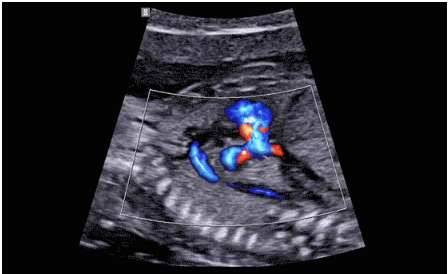

CrystalLive?是三星最新的超聲成像引擎,同時(shí)增強(qiáng)了2D圖像處理能力、3D渲染能力和彩色信號處理能力,能夠在復(fù)雜情況下提供出色的圖像性能,具備檢測外周血管、微循環(huán)血流的能力。

3D/4D成像方面,Hera i 10通過結(jié)合先進(jìn)的圖像渲染技術(shù),著重加強(qiáng)了邊緣和小結(jié)構(gòu)的可視化能力。